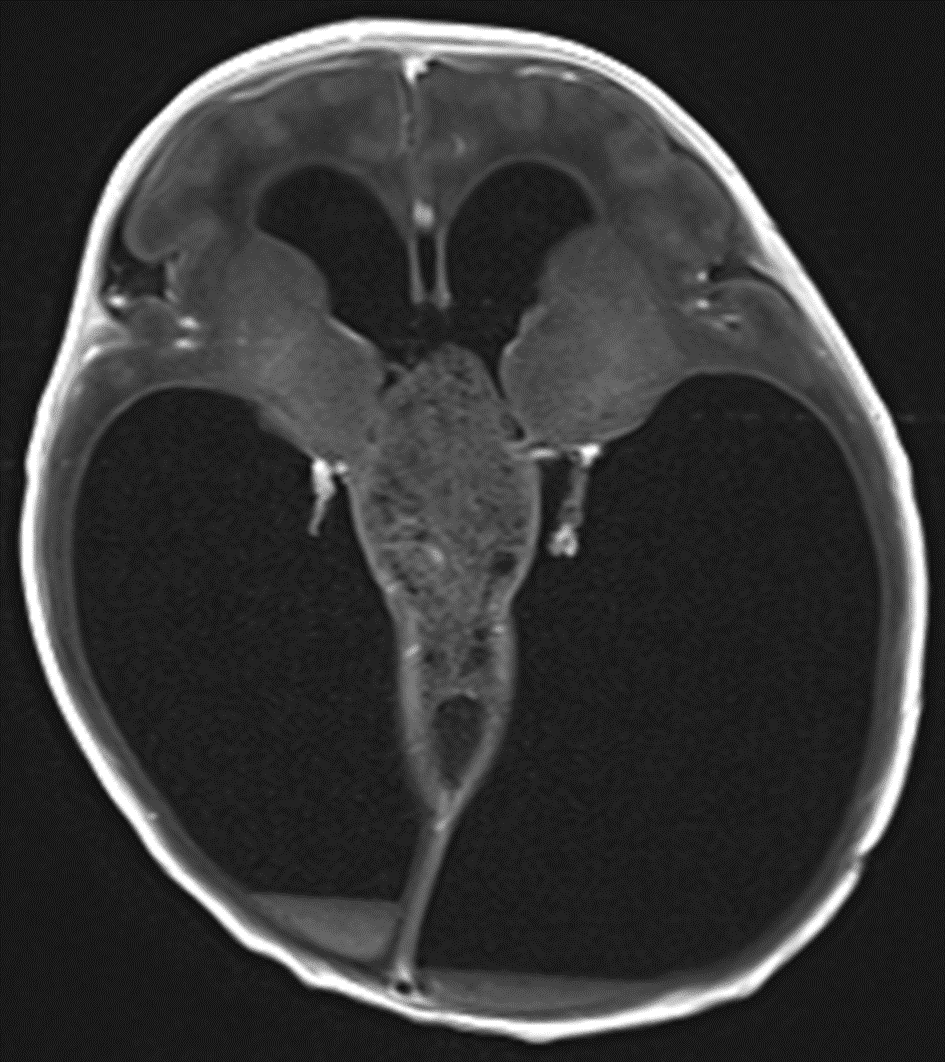

This mass demonstrates no appreciable corresponding enhancement.